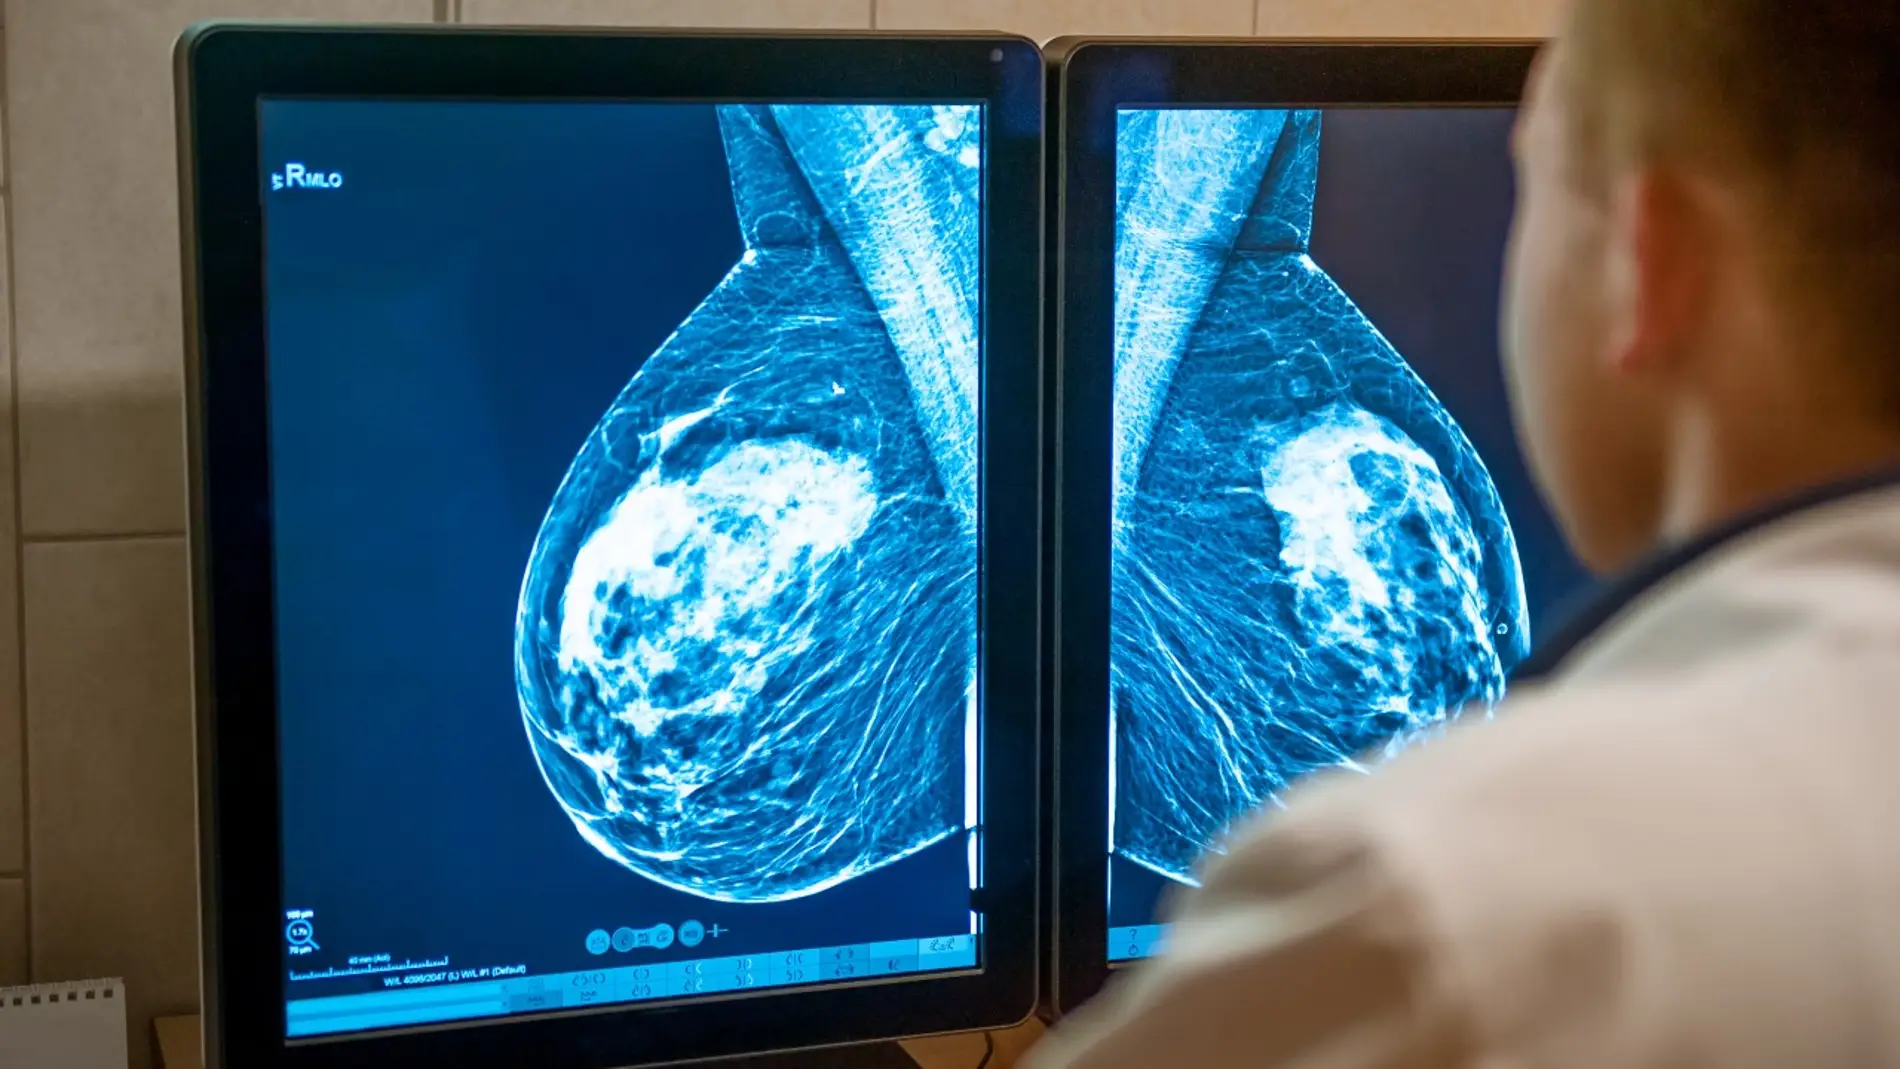

Investigadores chinos han desarrollado una nueva sonda para la formación de imágenes capaz de detectar con exactitud los tumores de mama, lo que permite extirparlos salvando al máximo el tejido mamario sano. El estudio, publicado en Science Traslational Medicine, se ha probado por ahora en ratones.

Un nuevo estudio, publicado esta semana en la revista Science Traslational Medicine, muestra una sonda de imagen capaz de detectar con exactitud los tumores antes de la operación, lo que permite extirparlos salvando al máximo el tejido mamario que no está afectado.

La nueva tecnología, desarrollada por investigadores de varias universidades chinas, podría cubrir la necesidad de métodos que identifiquen con precisión los márgenes tumorales durante este nuevo abordaje quirúrgico.

Para conseguirlo, el equipo diseñó una sonda de imagen y un método de incubación rápida que detecta una proteína llamada TROP2, elevada en la mayoría de los cánceres de mama. Probada en ratones, la sonda funciona con rapidez y puede utilizarse en medio de una intervención quirúrgica, con el fin de guiar la extirpación de estos tumores.

Es más, la sonda también distinguió con éxito lesiones mamarias benignas y malignas en las muestras de 26 pacientes con cáncer de mama.

Los autores destacan que se trata de un procedimiento rápido que requiere solo 15 minutos, aunque su objetivo futuro es acortar aún más el protocolo y probar la sonda en grupos de pacientes más amplios, concluyen.